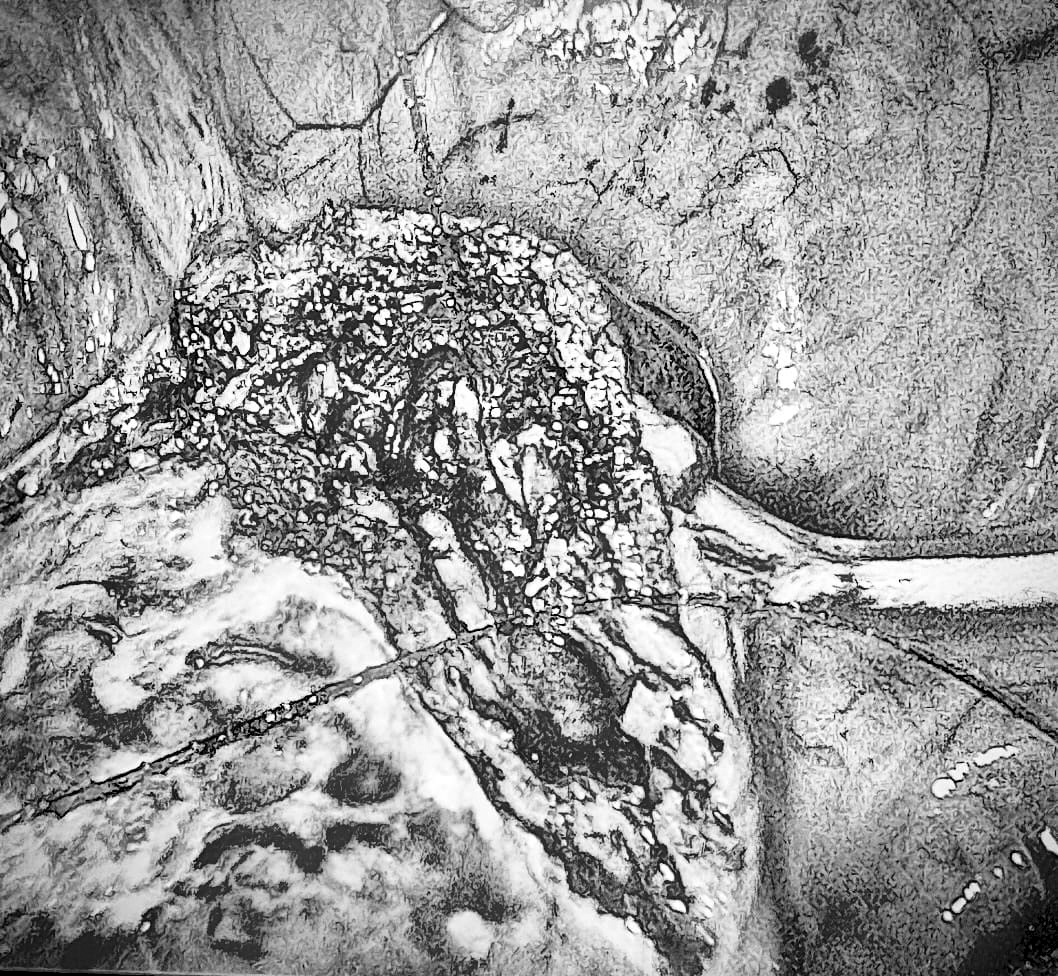

En el Servicio de Ginecología del Hospital Central del Instituto de Previsión Social seguimos escribiendo historias de salud y esperanza gracias al equipo humano de endoscopía ginecológica, encabezado por el Dr. Rafael Adorno, la Dra. Yodia Alvariza y la Dra. Catalina Gómez, junto con los anestesiólogos Dr. Javier Paiva y Dr. Mathias Quintana, se llevó a cabo con éxito una cirugía de istmoplastia laparoscópica.

¿Qué es el istmocele?

El istmocele es una alteración en la cicatrización de la cesárea que provoca un "defecto" en la pared uterina. Sus síntomas más frecuentes son: